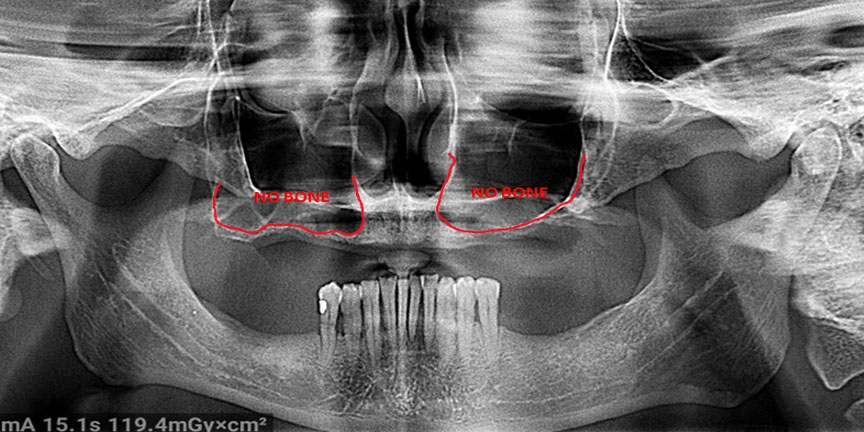

Severe Bone Loss

ImageImage